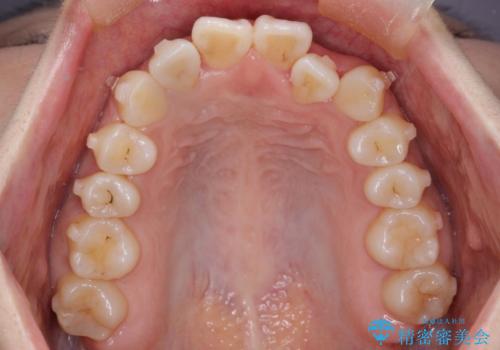

- 前歯の歯並びの改善を希望され来院された患者様です。

初診時の歯並びの状態としては、上下ともに全体に及ぶの中等度のがたつき(叢生)があり、全特に左上の前歯は1本だけ引っ込んでいる状態でした。

抜歯は行わず上顎の奥のスペースを利用して歯をスライドする方法の他に歯列弓の拡大やディスキング(歯と歯の間の隙間を作る処置)を行い叢生を改善しました。

歯の大きさの不揃いが原因の正中のズレは、ディスキング量を調整することで合わせました。